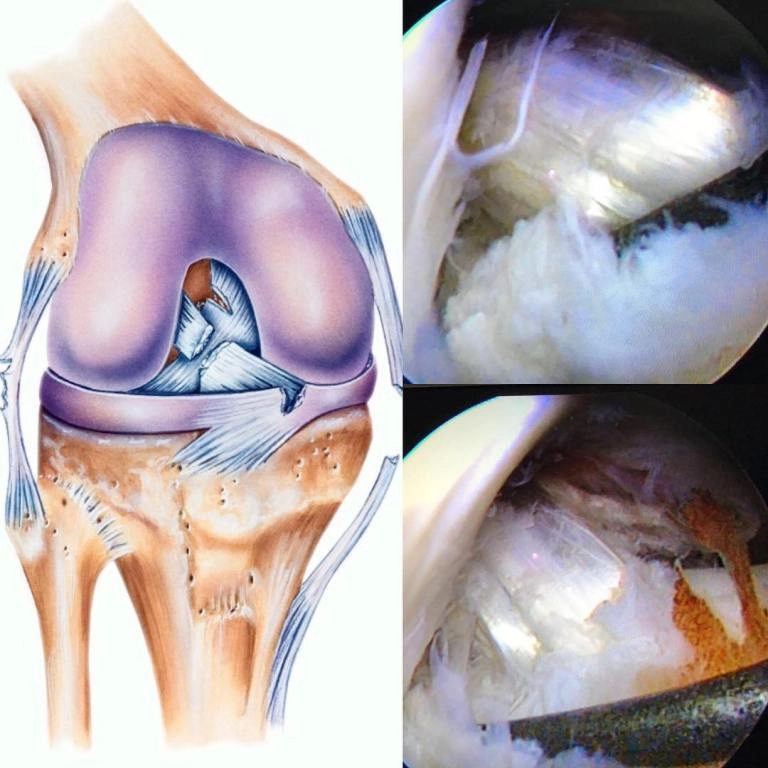

• Артроскопия проводится с использованием щадящих технологий, позволяющих лечить повреждения плечевого, коленного, локтевого

и голеностопного сустава с минимальной травматизацией.

• Для людей, столкнувшихся с повреждениями колена,

актуально будет лечение разрыва мениска.

Врач выполняет операции с учетом возраста пациента, уровня физической активности и индивидуальных особенностей организма.